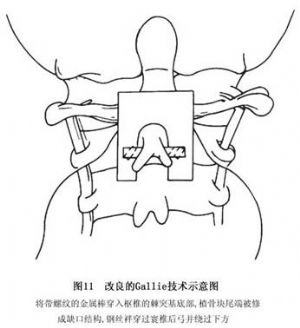

近年来,Mah及其同事提出了改良的Gallie融合技术。其特点是在颈2棘突基底部穿过一枚较粗且带螺纹的金属杆(图11)。在棘突两侧各留1cm长度,使固定钢丝(或钛丝)向下绕过金属杆的两端后,在中线处拧紧。